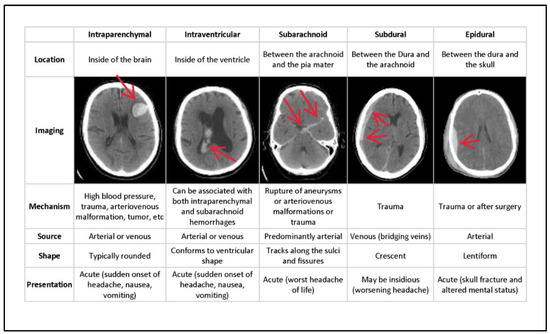

In general, ICH is divided into six categories of hemorrhages. Epidural (EPD) pain occurs as a result of an injury to the dura mater and skull. Intraparenchymal (ITP) happens when blood pools in brain tissues; intraventricular (ITV) occurs when bleeding enters the brain’s ventricular system. SBC arises when blood gathers beneath the arachnoid and the pia mater. Subdural (SBD) bleeding occurs when blood flows between the dura mater and the arachnoid mater, and some (SOME) bleeding is defined as any hemorrhage [8]. Figure 1 depicts the many forms of hemorrhages, with the sixth being classified as SOME or ANY hemorrhage. The different types of hemorrhage occur in different areas of the skull.

Figure 1 depicts the type of bleeding, as well as the location and specifics of the hemorrhage. Even though the output from the neural network does not provide any location information, this is used to pinpoint the bleeding. Epidural (EPD), Intraparenchymal (ITP), Intraventricular (ITV), Subarachnoid (SBC), Subdural (SBD), and more designations are conceivable (SOME). If there is some hemorrhage, the final label will be correct. Multiple hemorrhages can occur at the same moment in some real-life settings [10].

Figure 1. Types of hemorrhages and their respective location inside the skull [9].